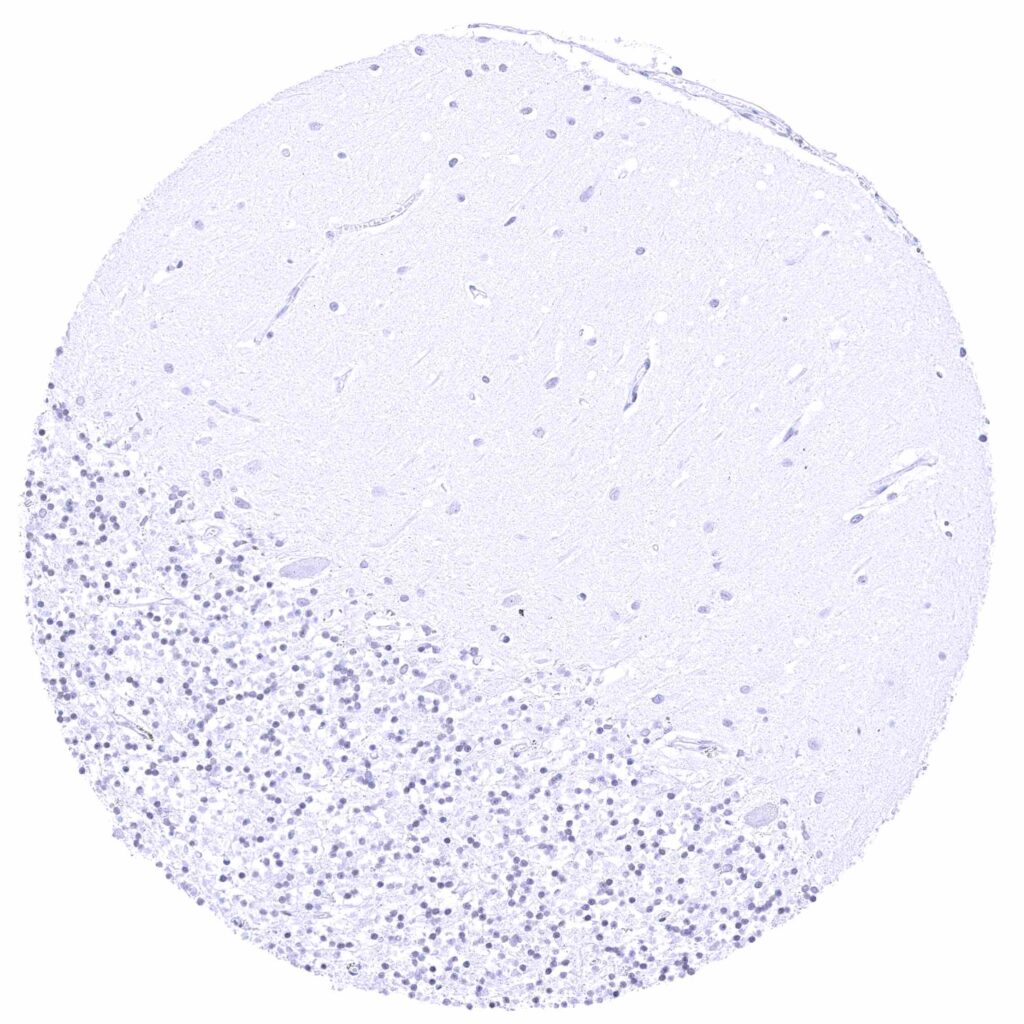

Cerebellum (molecular layer, Purkinje cell layer, granule cell layer)

Cerebellum (white matter)

Cerebrum (grey matter)

Cerebrum (white matter)